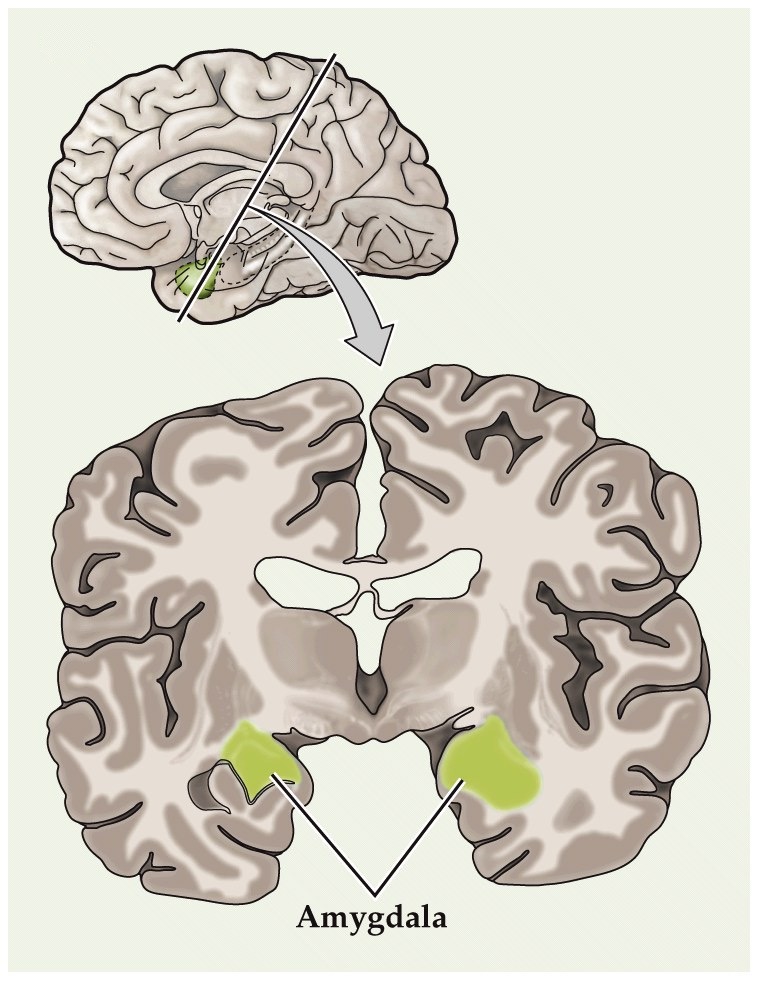

Amygdala

-

amgydala is in the anteior-medial part of the temporal lobe. Rostral to hippocampus

three major functional and anatomical subdivisions

medial group

- connections with olfactory bulb and olfactory cortex

basal-lateral group

- large in humans

- major connections to orbital and medial prefrontal cortex of frontal lobe and association cortex of anterior temporal lobe

central and anterior group

- connections to hypothalamus and brainstem (visceral sensory structures like nucleus of solitary tract and parabrachial nucleus)

hypothalamus receives unprocessed sensory inputs, amygdala receives processed sensory inputs (cortex and thalamus)

highly complex stimuli often needed to evoke response in amygdala (e.g. facelike neurons)

Crude lesion studies

- John Downer (London in 1950’s) removed the temporal lobes of monkeys and witnessed weird emotional behaviors

- Unable to recognize objects, although not blind (why?)

- Bizarre oral behaviors

- Hyperactivity and hypersexuality, making physical contact with virtually anything

- No longer showed fear. Neither to humans or to snakes

- Eventually the fear behaviors was narrowed down to a region called the amygdala through selective lesion studies

Patients with amygdala damage exhibit diminished emotional fear recognition and expression

Patient S.M. can’t recognize the emotion of fear in photographs. She also exhibits little fear herself (e.g. to dangerous animals, scary houses, films, etc)

patient SM has rare autosomal recessive condition called Urbach-Wiethe disease. Disorder of bilateral calcification an atrophy of anterior-medial temporal lobes. Both amygdalas are extensively damaged. Little to no injury of the hippocampus.

She has no motor or sensory or intelligence or memory or language impairment. However she can’t recognize the emotion of fear in photographs. Furthermore, she exhibits little fear herself (to dangerous animals, scary houses, films, etc).

Patients with amygdala damage exhibit diminished emotional fear recognition and expression

Adolphs et al., 1995. Subject with bilateral amygdala lesions was asked to draw facial expressions of emotions.